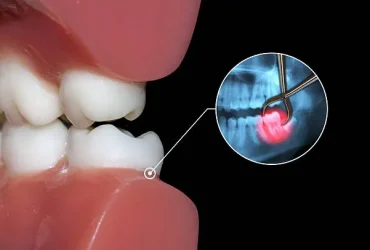

ฟันคุดคือ อะไร

ฟันคุดคือ ฟันกรามซี่ในสุด ทั้งหมด 4 ซี่ บน ล่าง ซ้าย ขวา ไม่สามารถขึ้นได้ตามปกติเพราะพื้นที่ไม่เพียงพอให้ฟันสามารถขึ้นมาได้ บางซี่อาจจะโผล่ขึ้นมาเล็กน้อย และบางซี่ถูกฝั่งอยู่ในกระดูดขากรรไกร อาจจะขึ้นตรง เอียงหรือนอนในแนวราบส่วนใหญ่ฟันคุดมักพบว่าอยู่ที่ฟันกรามซี่ล่างในสุดและพบมากสุดในช่วงอายุ ประมาณ 16 – 25 ปี หรืออาจจะช้ากว่านั้น

ทำไมต้องผ่าฟันคุด

เพื่อป้องกันปัญหาเกี่ยวกับช่องปาก ฟันผุ เหงื่อกอักเสบ ฟันซ้อมเก ไม่ควรปล่อยให้ฟันคุดฝั่งอยู่ในขากรรไกร เพราะอาจะทำให้แนวฟันอื่นเสียหายจากการดันตัวของฟันคุด และที่สำคัญคือส่งผลให้มีอาการปวดฟันคุดรุนแรง